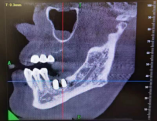

(李女士种牙经过)

术后李女士感觉良好,对该次数字化种植牙体验非常满意!

(术后图示)